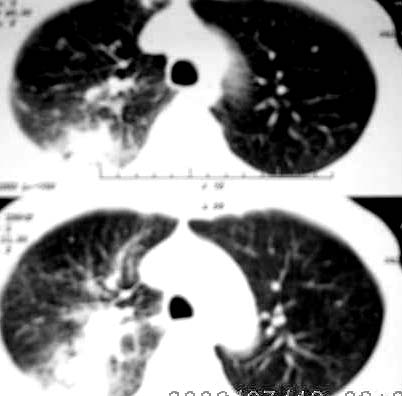

以下是引用jiangjing在2006-7-20 19:22:00的发言:[br]右侧肺门见有软组织肿块,边缘不规则,不光整,其周围肺内见炎性片状影,胸片示水平裂呈弧形上移,右上叶支气管狭窄,考虑右肺中央型肺癌伴阻塞性肺炎部分肺不张。

以下是引用1983在2006-7-20 21:53:00的发言:[br]右侧中央型肺癌伴阻塞性肺炎.

以下是引用卜一在2006-7-20 14:13:00的发言:[br]图象质量差了些,首先考虑:中心性肺癌伴阻塞性肺炎.因发生在右肺上叶尖后段,而且外带见二个空洞影,次考虑:不排除肺结核